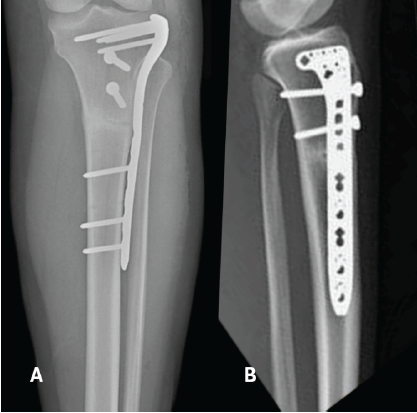

Fastly, a lateral tibial pre-modulated locking plate was applied to prevent further fracture propagation and avoid prolonged cast immobilization (Fig. 4). The same unlocked knee extension brace was recommended, along with a full weight-bearing protocol. Ten months after the plating procedure, the proximal tibial stress fracture had consolidated, with the KOOS score evaluated at 90.5 at that time (Fig. 5). Later, the patient underwent the removal of all hardware successfully (Fig. 6).

Figure 4: Anteroposterior view (a), lateral view (b) demonstrate the immediate post-surgical view of fracture fixation with lateral tibial pre-modulated locking plate.